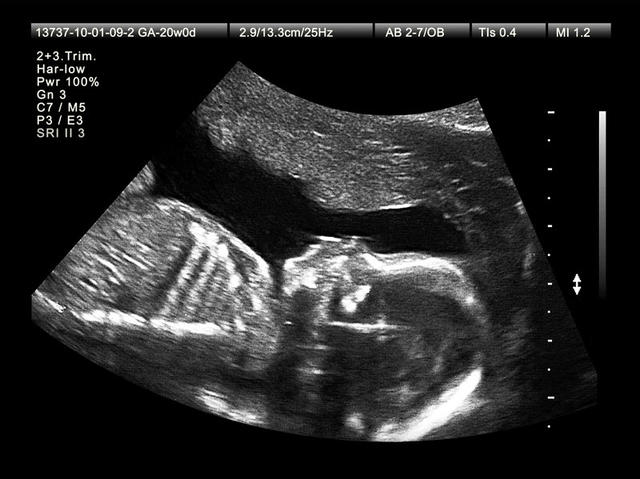

超声波往往被用于产前筛查。怀孕妇女可以选择的几种产前筛查中,这只是其中一种。图片来源:npr.org